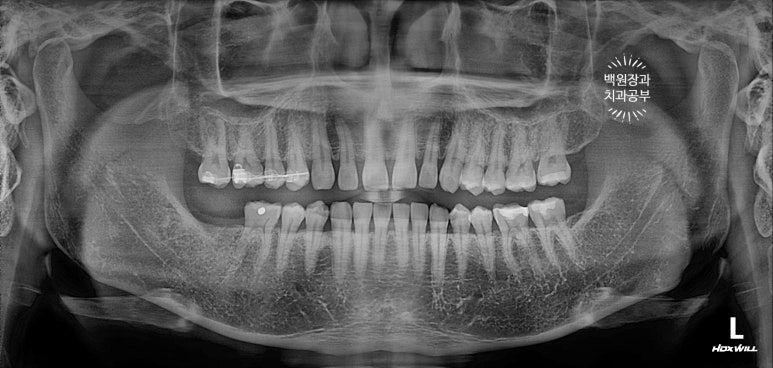

먼저 전체 치과용 파노라마 엑스레이부터 볼까요?

어색하게 깡뚱하게 있는 치아가 보이시나요?

아래턱 오른쪽 두번째 큰어금니가 신경치료는 되어있지만, 이미 뿌리만 남은 상태로 오셨어요.

노란색으로 동그랗게 표시해놓은 치아가 오른쪽 아래 두번째 큰어금니입니다.

오른쪽 아래 두번째 큰어금니가 뿌리만 남아있은지가 너무 오래되서, 그 공간으로 짝꿍 치아인 (대합치) 오른쪽 위 두번째 큰어금니가 꽤나 내려와 있었어요.

치과에서는 치아가 정출(extrusion)되었다고 표현합니다.

공간이 침범되어 있는 상태였기 때문에 선택을 해야하는 상황이었답니다.